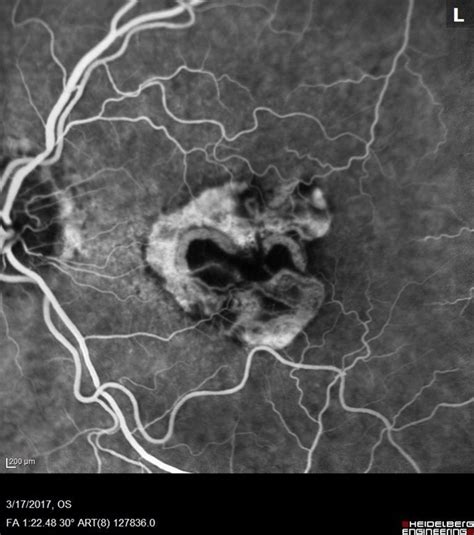

So, you think you might have neovascular AMD with active CNV OS ? Here’s what you can expect in terms of diagnosis and treatment. First, your eye doctor will perform a comprehensive eye exam, which will include a review of your medical history, a visual acuity test to check how well you can see, and a dilated eye exam. During the dilated eye exam, your doctor will use special drops to widen your pupils, which allows them to see the back of your eye, including the macula and retina, in detail. Your doctor might also use optical coherence tomography (OCT), which is a non-invasive imaging technique that provides detailed cross-sectional images of the retina. The OCT can help detect fluid or other changes in the macula caused by CNV . Another diagnostic tool is fluorescein angiography (FA). This involves injecting a dye into your arm and taking pictures of the blood vessels in your eye as the dye circulates. This helps identify leaking blood vessels. The most common treatment for neovascular AMD is anti-VEGF injections. VEGF (vascular endothelial growth factor) is a protein that promotes the growth of new blood vessels. Anti-VEGF drugs block this protein, which helps to stop the growth of new, abnormal blood vessels and reduce leakage. Injections are typically given directly into the eye on a regular basis. Other treatment options include photodynamic therapy (PDT), which uses a light-sensitive drug and a special laser to destroy the abnormal blood vessels. And, in some cases, your doctor might recommend laser photocoagulation to seal off the leaking blood vessels. The best course of action is different for each patient. Be sure to discuss all options with your eye doctor.